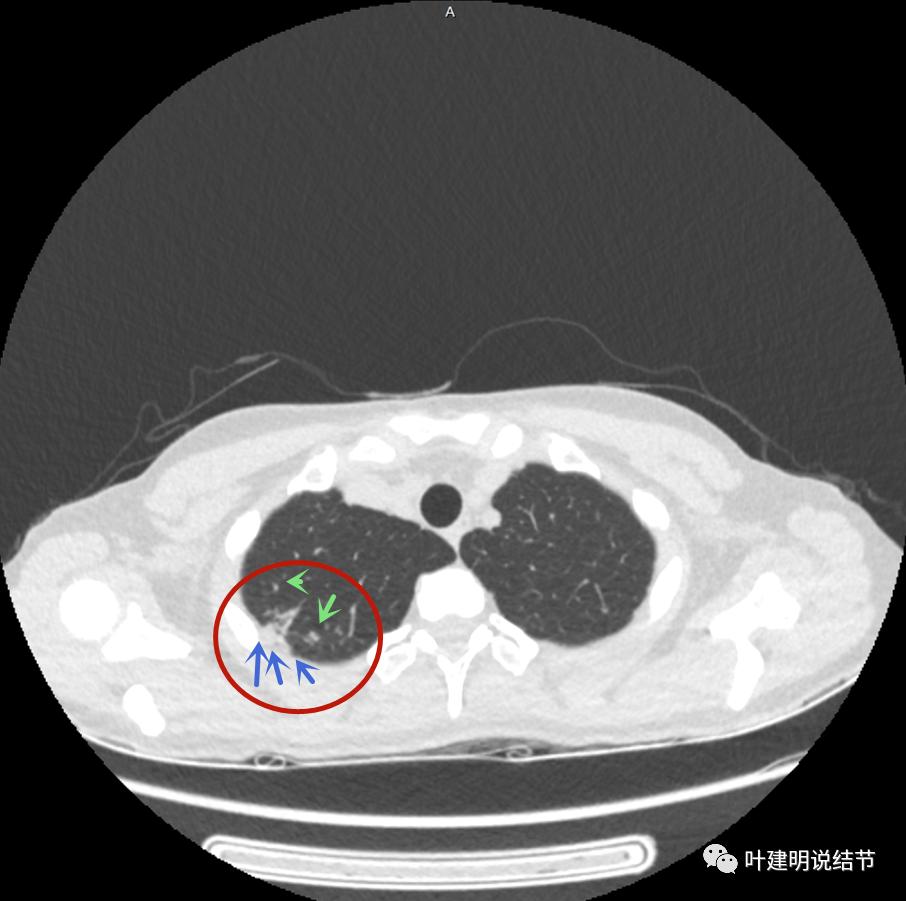

下面是今年复查的平扫片子,来看看有什么变化:

病灶邻近胸膜异常增厚(蓝色箭头)

有卫星灶(绿色箭头),邻近胸膜明显增厚,且模糊,边不清

邻近胸膜增厚

主病灶此层面似三角形,邻近胸膜增厚(蓝色箭头),结节实性部分密度较高(粉色箭头),边缘显模糊(砖色箭头)

上图与恶性较为符合,空洞性病灶,壁厚薄不均,增厚部分还凹凸不平(细红色箭头所指)

上图磨玻璃部分密度过低,且与正常肺组织界限模糊(砖色箭头),粉色箭头示囊壁密度过高的点状,蓝色箭头示邻近胸膜处的增厚

上图也像恶性,但整个囊壁的密度感觉过高了点,边缘磨玻璃淡、散且模糊,邻近胸膜有增厚

上图病灶的边相对比较光,没有毛刺征,邻近胸膜增厚

上图病灶边缘比较平直,没有膨胀性(桔色箭头),旁边的磨玻璃影淡且界限不清,邻近胸膜增厚。

再看影像印象:病灶较1年前有所进展,部分层面像恶性,囊壁厚薄不均,内面有小突起。但邻近胸膜增厚,旁边的磨玻璃部分散且淡,边界不清,实性部分边相对较光,囊壁有点状过高密度。良性可能性大些,恶性不能除外。